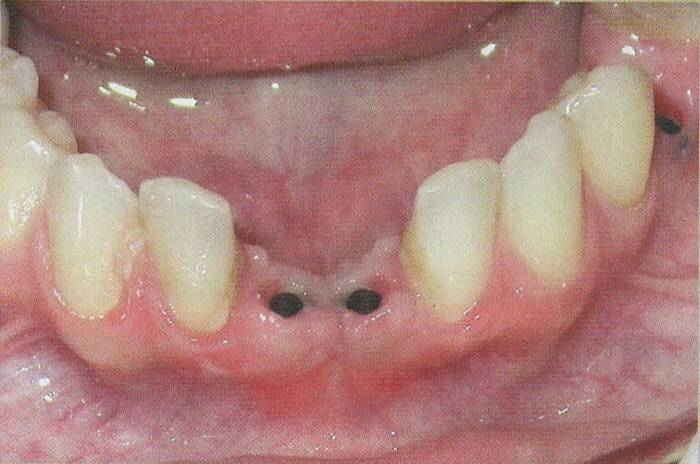

CERAMICHE SU IMPIANTI

Per l'esecuzione delle impronte vengono usati materiali di prima qualità perchè la precisione delle impronte facilita la costruzione del manufatto e questo è un passaggio fondamentale per la buona riuscita della protesi.

In questo studio vengono eseguite ceramiche di ultima generazione quali la zirconia ceramizzata, le ceramiche estetiche in disilicato senza trascurare le tradizionali metalceramiche. Il disilicato è un materiale altamente estestico che conferisce alla corona protesica un aspetto naturale e con questo materiale si possono creare manufatti con uno spessore molto ridotto.